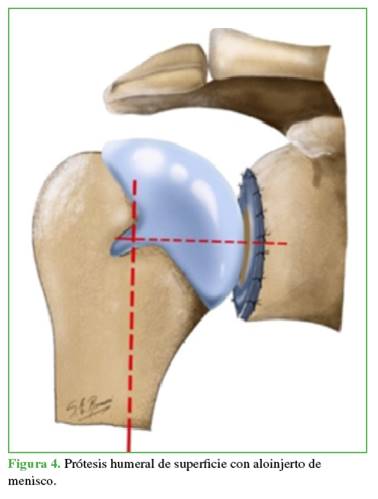

Tiempo humeral: luego de la luxación controlada y la preparación de la cabeza humeral, se realizó la artroplastia humeral de superficie no cementada que, en todos los casos, fue la misma (Copeland Mark III®, MacroBond; Bio-met, Warsaw, Indiana, EE.UU.) (Figura 4).

En respuesta a esta difícil decisión terapéutica, se ha introducido el concepto de “compra de tiempo y calidad de vida”,20 sobre la base de opciones de interposición biológica para retrasar el deterioro articular sin comprometer futuras cirugías. Uno de los pioneros en proponer esta técnica fue Burkhead,9 quien asoció la hemiartroplastia con autoinjertos (cápsula, fascia lata) o aloinjertos (Aquiles), y obtuvo resultados variables, pero alentadores para ganar tiempo y mejorar la calidad de vida. En este estudio, se eligió la interposición de menisco (que mejor se adaptara a la superficie articular) sobre la base de las experiencias positivas de supervivencia de los trasplantes en rodillas degenerativas de pacientes jóvenes, y por las ventajas mecánicas que ofrece: transmisión de cargas, menor estrés cartilaginoso, absorción de impacto, estabilidad, lubricación y nutrición condrocitaria.21 Asimismo, la forma del menisco externo permite que, al unir sus cuernos anterior y posterior, se adapte perfectamente a la glena y la cabeza humeral, disminuyendo la presión glenohumeral en un 10% al dispersar las fuerzas.22,23 La interposición de injerto meniscal busca mejorar la congruencia articular y actuar como agente biológico de articular. Dentro de las opciones de preservación de meniscos, tres métodos han sido los más utilizados: congelados, congelados con irradiación gamma y criopreservados.24 En diferentes estudios, se ha comunicado que el menisco cadavérico debe ser criopreservado no liofilizado ni irradiado para conservar su estructura biológica y no perder sus propiedades biomecánicas.21,24-26 La mayoría de los estudios no especifican el método de conservación del aloinjerto meniscal. En todos nuestros pacientes, se utilizó aloinjerto de menisco criopreservado no irradiado, lo que podría explicar nuestros buenos resultados clínicos al mantener su microestructura. En este estudio, hemos optado por realizar prótesis de superficie por varias ventajas: recrea mejor la biomecánica normal al conservar el centro de rotación humeral en comparación con la hemiartroplastia con tallo, reduce el tiempo quirúrgico y preserva el tejido óseo facilitando futuras revisiones.20